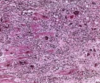

Asthma - mucus plugging, eosinophilic infiltration, thickened basement membrane, epithelial denudation, goblet cell hyperplasia

Microscopically, dense fibrosis and destruction of alveolar architecture.

Active fibrotic lesions composed of myofibroblasts

Aggregation of spindle cells with gray to pale purple matrix adjacent to dense fibrosis

Usual interstitial pneumonia (UIP) pattern